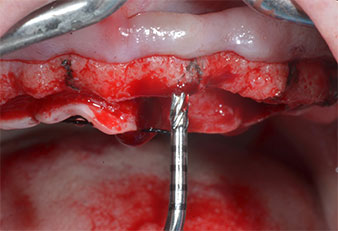

Para marcar las posiciones del implante y realizar la preparación piloto, se utilizó un inserto piezoeléctrico (Piezomed I1) con revestimiento de diamante y forma de llama (figura 3). Se tomaron precauciones para realizar movimientos hacia arriba y hacia abajo, con una potencia reducida, una irrigación completa y una baja presión (por debajo de 300 g). A continuación, se aplicó un inserto piloto (Piezomed I2A/I2P) para aumentar el diámetro inicial de 2 mm de los sitios de implante (figura 4), seguido de un inserto de 3 mm (Fig. 5).

En el caso que nos ocupa, no se utilizaron los insertos Z25P ni Z35P debido a la existencia de un hueso posterior relativamente blando, que se trató sin problemas con el I3A/I3P.